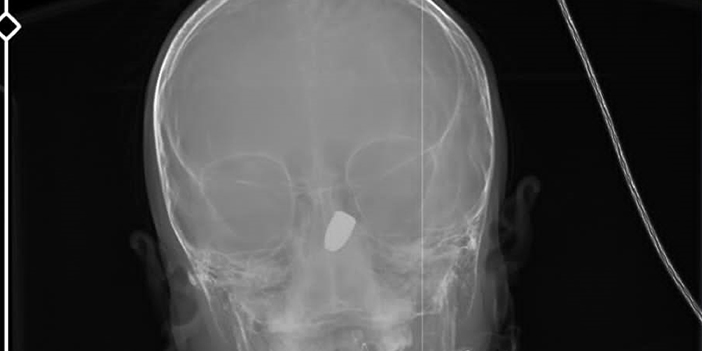

Olay, 10 Haziran'da Çukurçayır Mahallesi'nde meydana geldi. Site parkında arkadaşları ile oynayan Kerem Can Özdemir, birden kanlar içerisinde yere yığıldı. Çağrılan sağlık ekiplerince KTÜ Farabi Hastanesi'ne kaldırılan Özdemir'in çekilen tomografisinde başına yorgun mermi isabet ettiği tespit edildi. Olay ile ilgili başlatılan soruşturma sürerken, küçük çocuğun yere yığıldığı anlar da sitenin güvenlik kamerasına yansıdı. Silahı ateşleyenin belirlenmesi için İl Emniyet Müdürlüğü bünyesinde özel ekip oluşturuldu. Bölgede birçok güvenlik kamerasını mercek altına alan ekipler, şüphelinin izini sürüyor.

MERMİ 6 SANTİMETRE DERİNDE

Yoğun bakım servisinde tedavisi süren Kerem Can Özdemir’in, risk oluşturduğu için ameliyata alınmadığı belirtildi. Beyninin 6 santimetre derinine saplanan mermi çekirdeğiyle yaşam savaşı veren Kerem Can’ın 37 haftalık hamile annesi Fatma Özdemir, olaydan 2 gün sonra aynı hastanede erken doğum yaptı. Prematüre doğup, kuvözde tutulan bebeklerini kucaklarına almayı bekleyen aile, aynı hastanenin koridorunda bir yandan da yaralı çocuklarından gelecek iyi haberi bekliyor. Özdemir ailesi hem sevinci hem de hüznü bir arada yaşıyor.